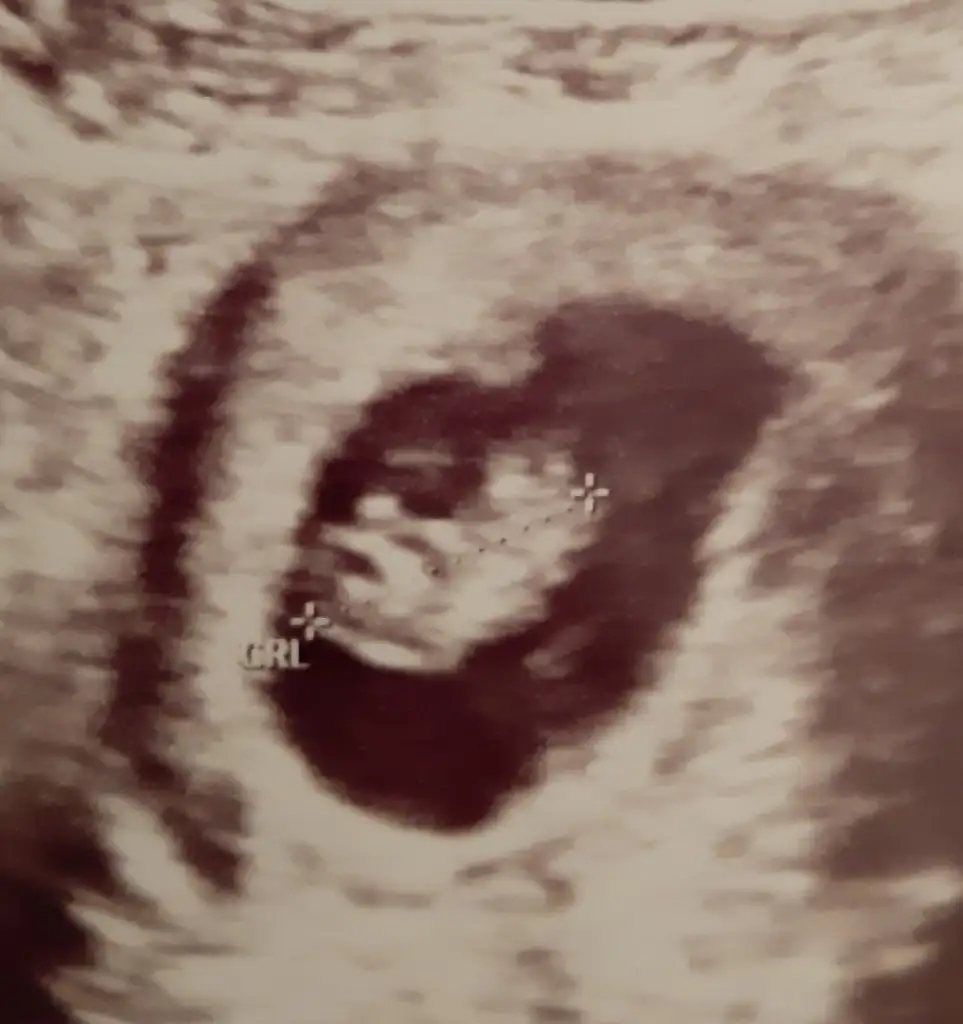

Netleşince anketimi oylarsanız sevinirimKesin olmamakla birlikte doktorumuzun ilk tahmini de kız![]()

Dün öğrendim sonucu sağlıklı bir kızçe annesi olucakmışım tahminlerin için teşekkürlerUsg kaç haftalık başka usg varsa paylaşın 11 +yada 12+